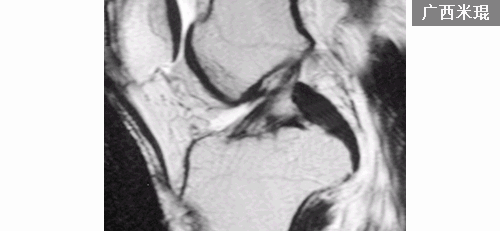

正常后交叉韧带的MRI表现:各序列均为低信号。矢状位韧带为凸面向后的弓形,边缘光滑。

矢状位上弓形的后交叉韧带形成一个135度夹角。

MRI阅片时要注意半月板-股骨韧带对后交叉韧带的影响,其在矢状位后交叉韧带弓形的上下方可见到小的、边缘清晰的低信号影。